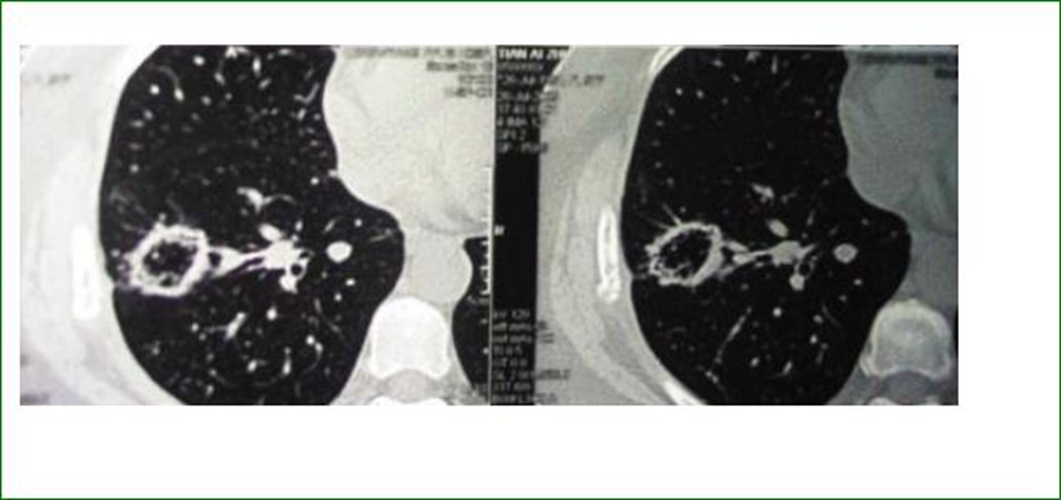

肺腺癌圖片

轉移性肺腺癌怎麼治療

右上肺腺癌

右下肺腺癌 的